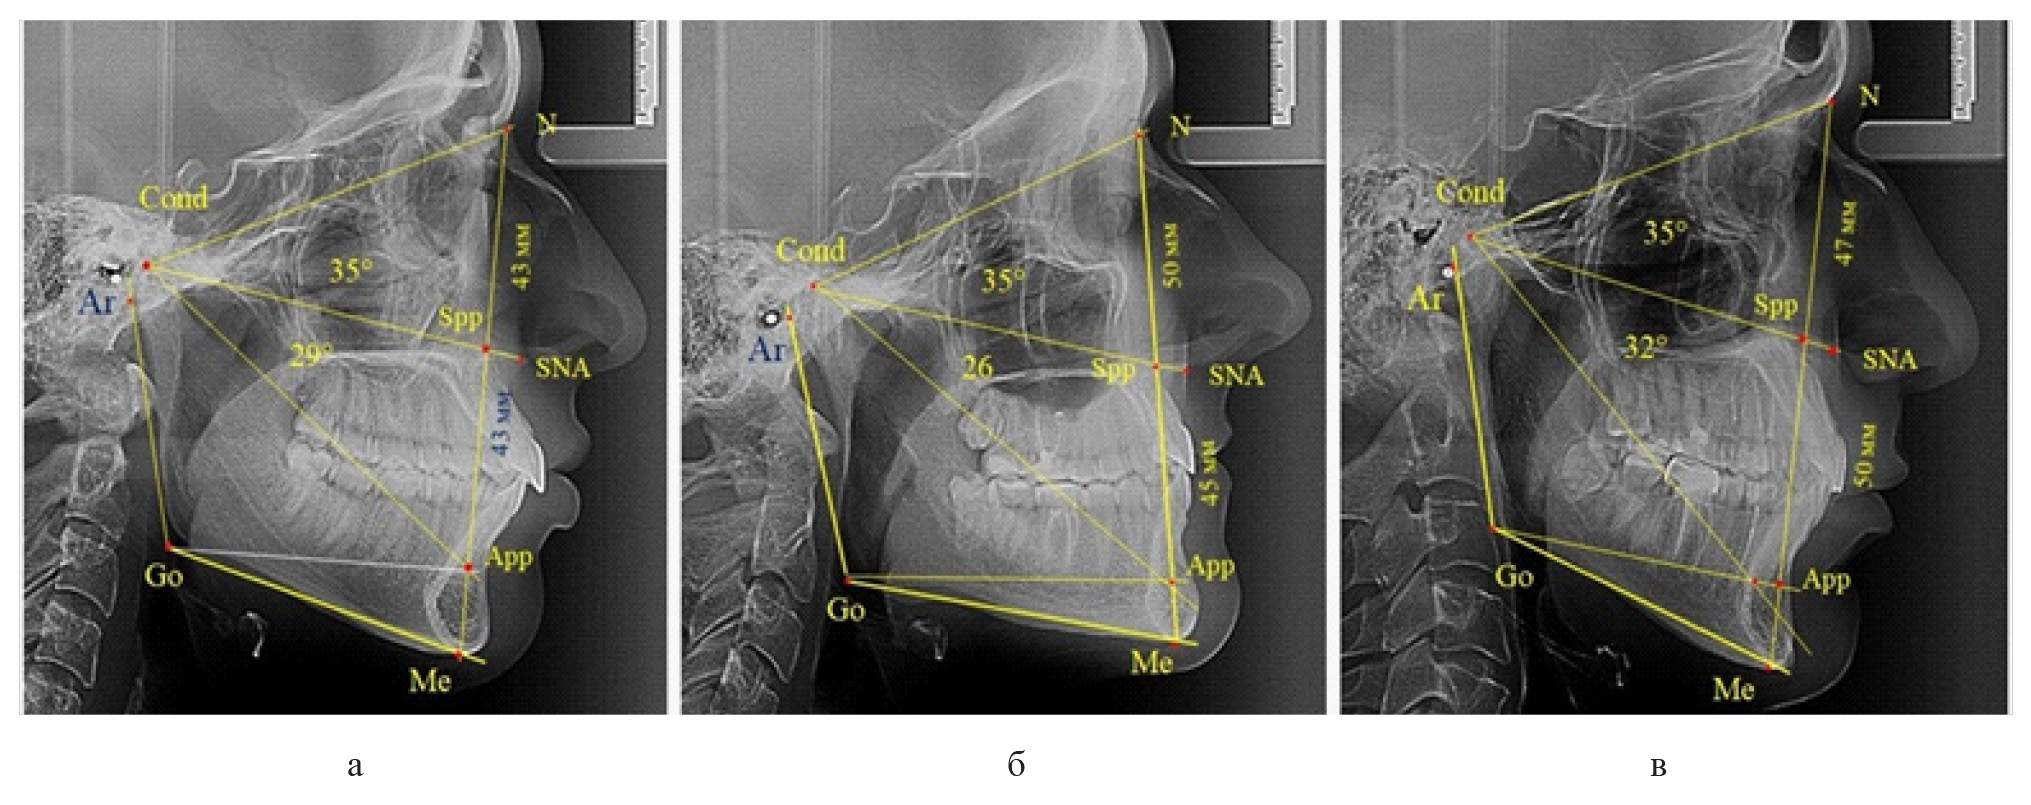

У 6 человек [(10,71 ± 4,13) %], отмечалось увеличение параметров гнатической части до уровня физиологического вертикального показателя, а у 2 человек [(3,57 ± 2,48) %], незначительное снижение гнатической части (рис. 3).

Рис. 3. Сравнительный анализ ТРГ с оптимальными размерами носового отдела и оптимальными (а), укороченными физиологическими (б) и увеличенными физиологическими (в) размерами гнатической части лица

Признаки снижения высоты назального отдела вплоть до уровня горизонтального патологического типа при физиологической окклюзии были определены у 10 человек [(17,86 ± 5,11) %]. При этом параметры гнатического отдела соответствовали физиологической норме либо физиологическому горизонтальному типу (рис. 4).

Рис. 4. Варианты ТРГ с укороченными размерами носового отдела и оптимальными (а) и укороченными (б) размерами гнатической части